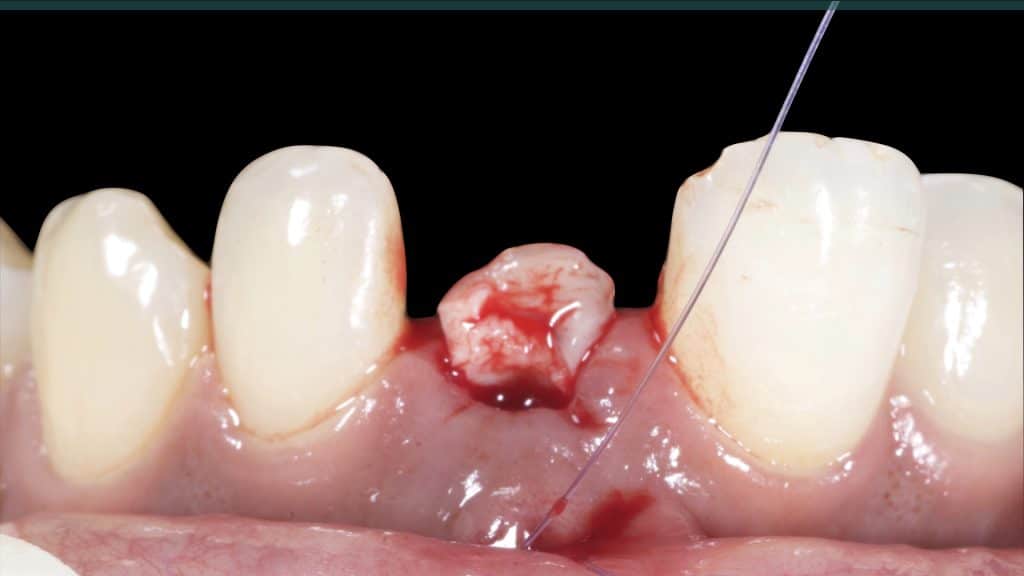

20 days post-op after suture removal